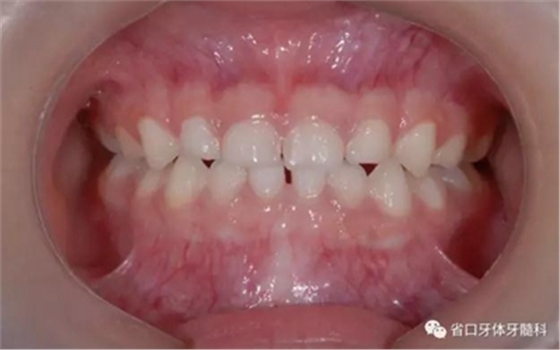

圖13 矯治結(jié)束后正面牙相(2015年3月)

頜墊舌簧適用于局部乳前牙反合的矯治或者替牙期局部前牙反合治療。